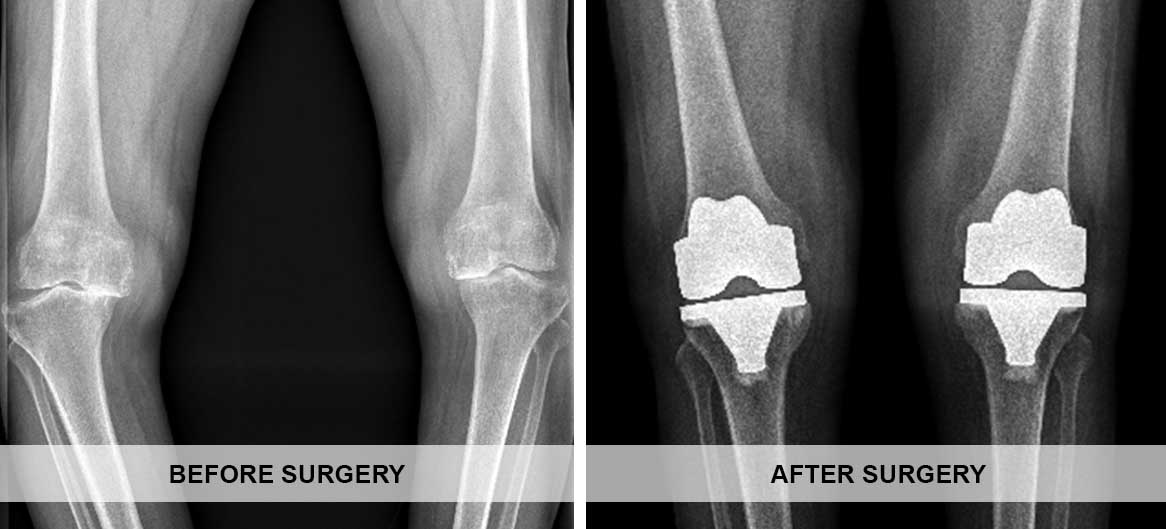

Total Knee replacement